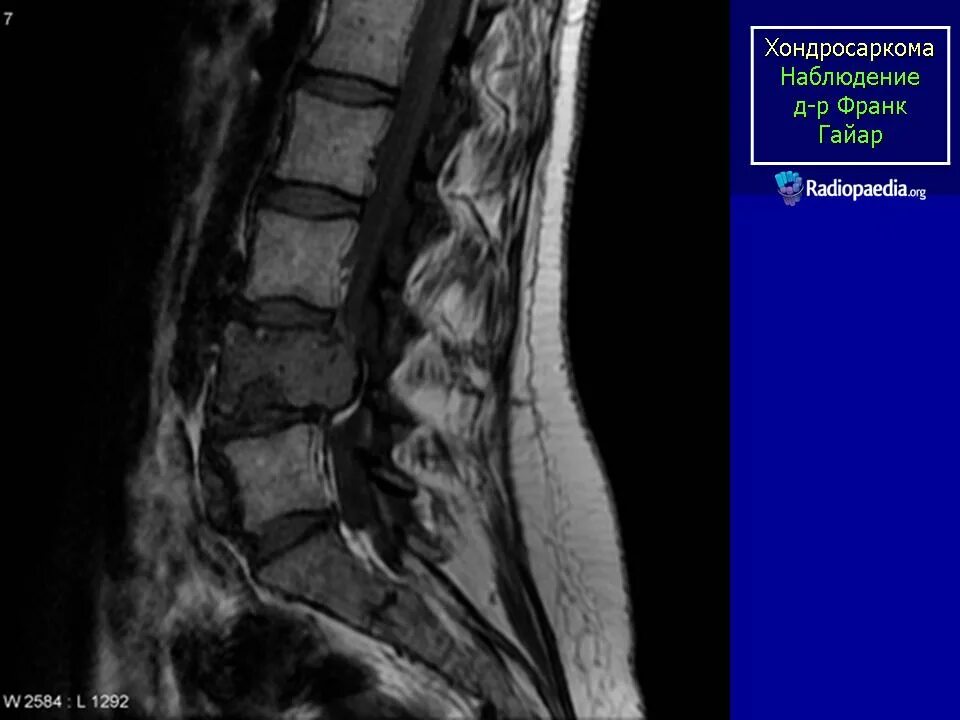

Саркома мрт